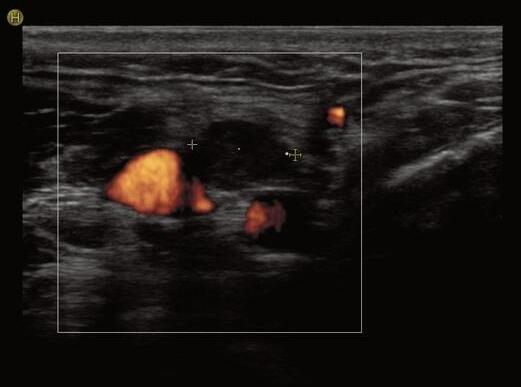

ECOGRAFIA DEL COLLO: STRUMENTO CHIAVE PER LA DIAGNOSI E IL MONITORAGGIO DEL CARCINOMA PAPILLARE DELLA TIROIDE

Giorgio Grani, Antonio Brunetti, Piernicola Garofalo, Giovanni Savoia, Michela Massa, Umberto Crocetti